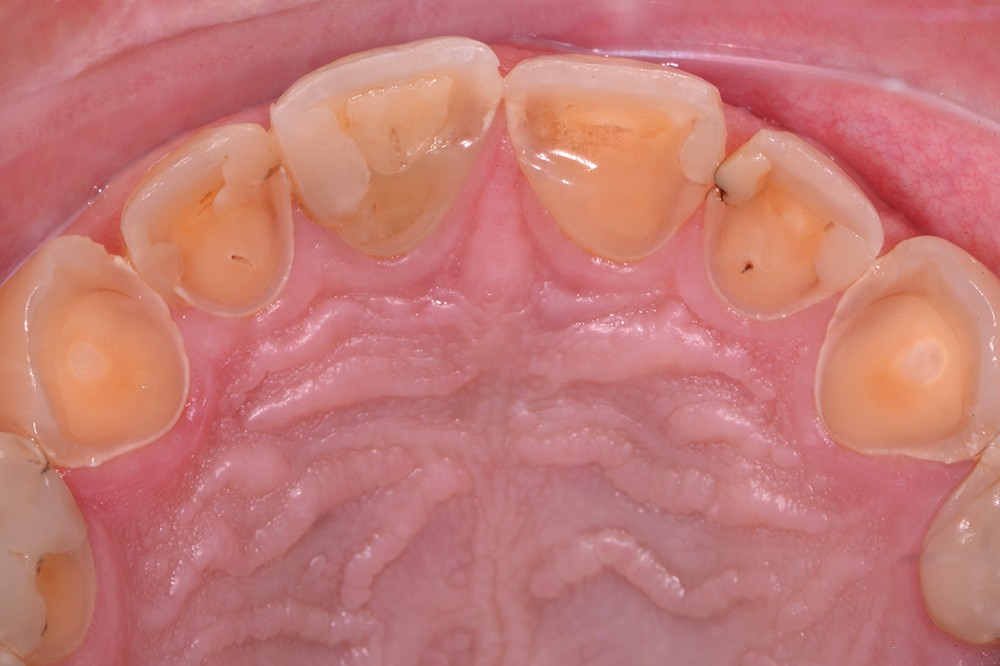

L’érosion survient lorsqu’une attaque chimique (solution acide, chélatant) rompt les liaisons intermoléculaires des tissus dentaires, potentialisant les différents autres modes d’usure mécanique (attrition, abrasion, abfraction) (fig. 5). L’aspect clinique des lésions érosives est polymorphe, mais, d’une manière générale, les surfaces sont lisses, en forme de cupules sur les sommets cuspidiens (fig. 6), de couleur satinée à terne. Les restaurations non affectées par l’environnement corrosif (amalgames, composites, alliages métalliques) surplombent généralement les surfaces amélaires et dentinaires adjacentes, alors que la morphologie dentaire est affectée. Les faces vestibulaires (fig. 7) et palatines (fig. 8) peuvent également présenter des lésions plus ou moins importantes, selon l’origine et le temps d’application de la source acide qui peut être d’origine extrinsèque (sodas, aliments acides) ou intrinsèque (sucs gastriques).